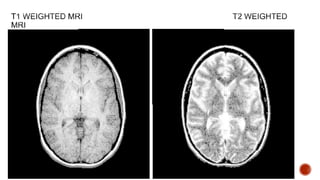

Radiofrequency and magnetic field pulses manipulated to

create different pulse sequences.

Based on the duration of RF pulse & the length of time -

different pulse sequences are obtained. Examples: T1, T2,

FLAIR, DWI, DTI etc.

Best for visualizing normal neuroanatomy

Sharp boundaries between grey matter, white matter, and csf

Useful in evaluation of cerebro-pontine angle, cistern &

pituitary fossa

BONE WHITE

WHITE MATTER LIGHT GREY

GREY MATTER MEDIUM GREY

WATER/CSF/AIR BLACK

T1 is the only sequence that

allows contrast enhancement

with GADOLINIUM.

Contrast enhanced structures

on T1 appears white

Less distinct boundaries between white and grey matter

Best for displaying pathology

Useful in demyelination, edema & tumour infiltration

GRAY MATTER MEDIUM GRAY

WHITE MATTER DARK GREY

CSF AND WATER WHITE